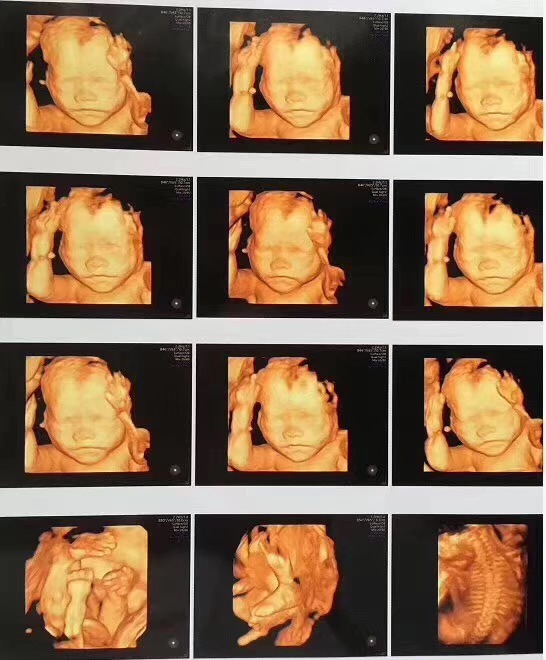

GE高清四维彩超

佛山都市妇产医院使用的是美国进口的GE高清四维彩超,可直观、立体、多方位观察孕妇宫内胎儿的活动图像、生长发育情况,高清显示腹中宝宝的实时动态“动画”,直观了解宝宝的一举一动。

孕中期超声检查(四维彩超)的最佳时间是22~26周,这个时段胎儿的肢体及各主要脏器已经全部发育,羊水适中,胎儿活动度大,体表也比较丰满,有利于胎儿超声成像和畸形筛查。